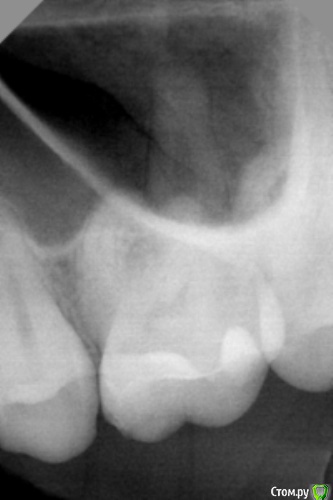

dr.Dre Опубликовано 11 апреля, 2016 Поделиться Опубликовано 11 апреля, 2016 Добрый вечер,коллеги подскажите в чем может быть причина такого рентгена может градус тубуса неправильный,пользуюсь такими позиционерами.С передними зубами все нормально. Ссылка на комментарий

DR.P Опубликовано 11 апреля, 2016 Поделиться Опубликовано 11 апреля, 2016 Угол не тот - завален, я без позиционеров работаю, ассистента натренировал так, что никогда не ошибается, с первого раза. Отталкиваться нужно от положения зуба и положения датчика на небе. С позиционером не всегда удобно - он выставляет строгую параллель между датчиком и тубусом, но не всегда небо готическое и иногда приходится выставлять средний угол между тубусом и датчиком относительно зуба (по кривой) Ссылка на комментарий

Eddie Опубликовано 11 апреля, 2016 Поделиться Опубликовано 11 апреля, 2016 (изменено) Поищите метод "биссектриссы" по Цешинскому.При нем луч направляют перпендикулярно биссектрисе угла, образованного вертикальной осью зуба и вертикальной осью приёмника изображения (плёнка, визиографический сенсор) с центрацией на апекс исследуемого зуба. Изменено 11 апреля, 2016 пользователем Eddie Ссылка на комментарий